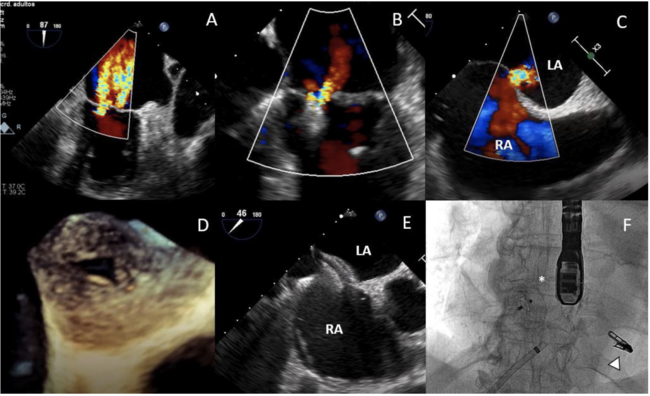

An 80-year-old female patient with atrial fibrillation and chronic kidney disease was admitted for heart failure. Severe functional mitral regurgitation (MR) and torrential tricuspid regurgitation (TR) (Figures 1A, 2A; Video Series) were detected on the echocardiogram.

She was rejected for a high-risk surgery and was referred for MitraClip repair. One XTR clip was implanted between A3-P3 leaflets with mild residual MR (Figure 1B; Video Series). After the procedure, the patient suffered abrupt oxygen desaturation. Echocardiogram revealed a right-to-left shunt through an iatrogenic atrial septal defect (Figures 1C, 1D). It was successfully closed with a 12-mm Amplatzer septal occluder (Figures 1E, 1F; Video Series) showing an immediate hemodynamic improvement.

Six months later, the patient continued with right heart failure. Right heart catheterization revealed a mean pulmonary artery pressure of 34 mm Hg and a right atrial pressure of 21 mm Hg (V-wave of 30). An interventional heterotopic tricuspid valve implantation was planned based on computed tomography (Figures 2B, 2C). Two TricValve self-expanding biological valves (P+F) were successfully implanted percutaneously (Figures 2D, 2E; Video Series).

At 24-month follow-up exam, the patient showed New York Heart Association class II, improvement in the 6-minute walk test (248 to 370 meters) and reduction in TR (Figure 2F; Video Series).